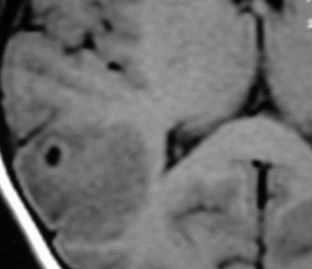

На КТ без усиления:

- Множественные изо- и гиподенсные участки, преимущественно в базальных ганглиях (76-88%) и в интра-субкортикальном слое.

- Размеры образований варьируют от 1см и менее до 3 см и более.

- Возможно распространение в заднюю черепную ямку.

- Перифокальный отек различной степени

- Масс-эффект.

- Кровоизлияния очень редко.

На постконтрастных КТ:

- Кольцевидное или узловое контрастирование.

Ободок усиления обычно тонкий и гладкий, но при больших поражениях встречаются толстые и неровные ободки. - Кольцевидное усиление -это зона интенсивной воспалительной реакции

Центральная область снижения плотности - некроз

По периферии расположена зона отека.